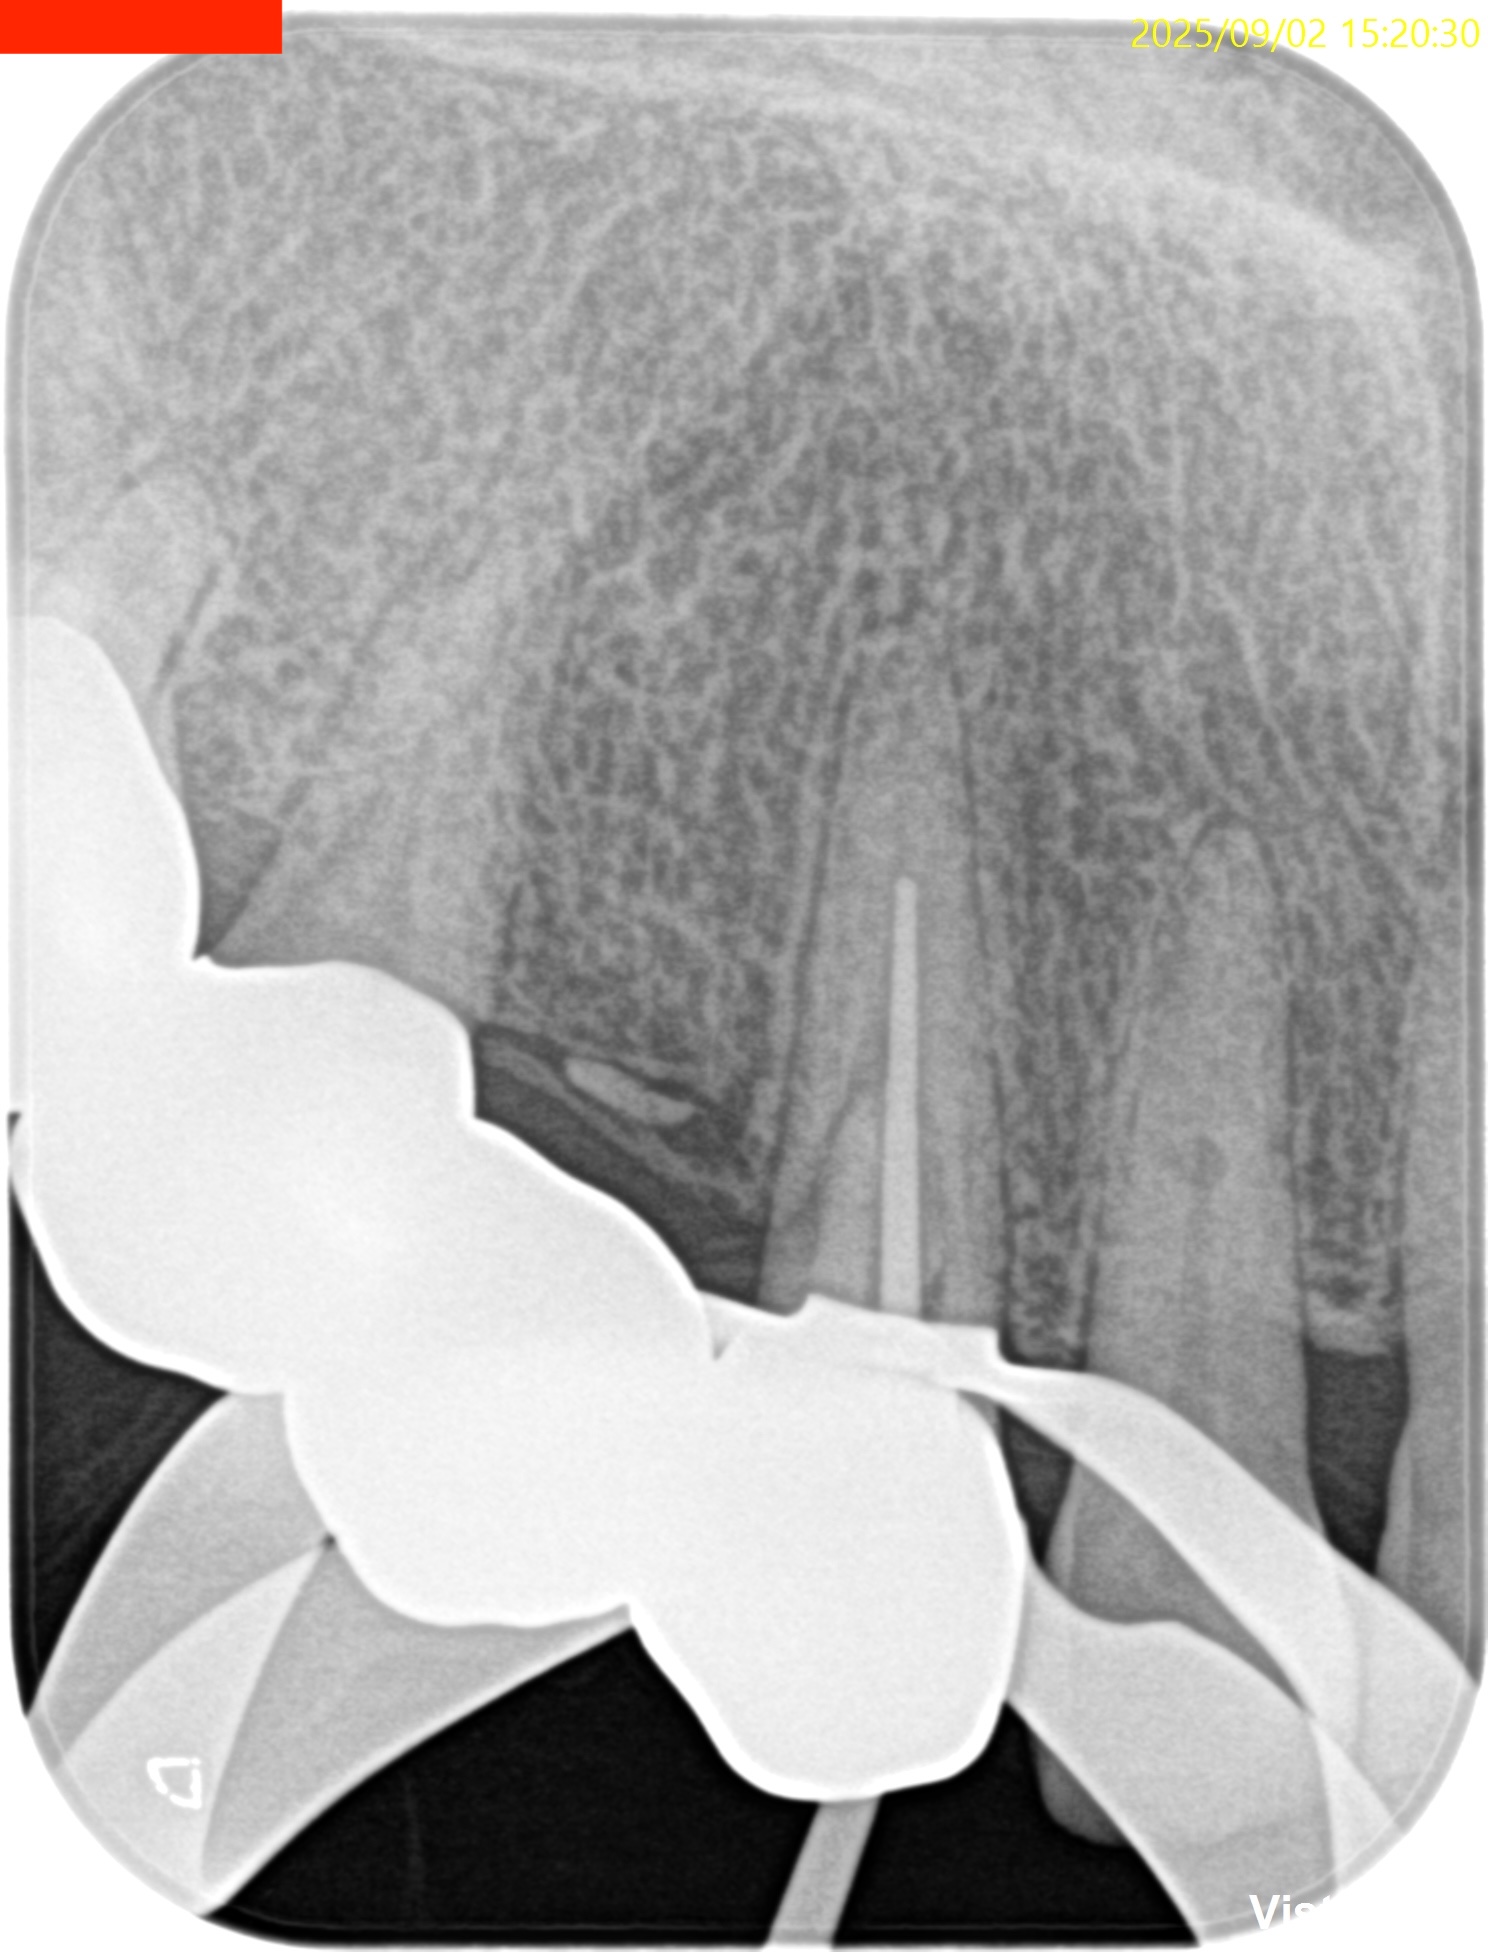

#6 Invasive cervical root resorption repair, RCT/Apicoectomy(2025.9.2)

Flapを開けてまず外部吸収部位を特定した。

外部吸収部位を90% TCAで科学的に処理した後に

EndoSequence BC Liner

で根管を水酸化カルシウムでカバーして充填し形態修正と研磨をした。

縫合後に、根管治療を試みるが…

とんでもない方向に穿孔していた。

ということでこの時点で非外科的な歯内療法の選択肢が消滅した。

ということで縫合して治療計画を変えることを説明する。